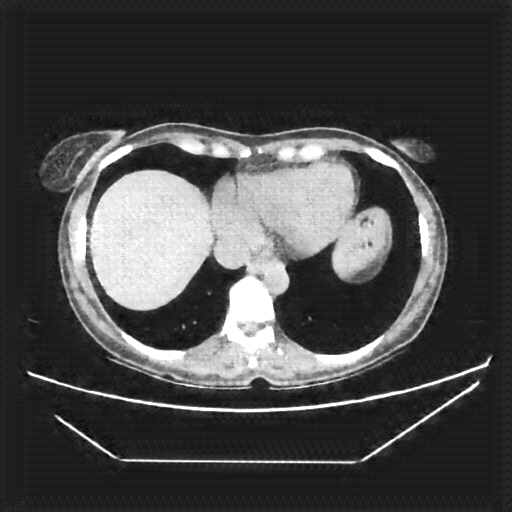

Reconstructed NATIVE CT scan (cycle consistency)

Full window (WL 1023.5, WW 4095 β†’ Low βˆ’1024, High +3071)

Lung window (WL -600, WW 1500 β†’ Low βˆ’1350, High +150)